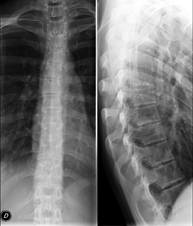

- Columna

- RX Columna cervical

Técnica mediante la cual, utilizando rayos X, se obtienen imágenes de la columna cervical para su estudio. Indicaciones: traumatismo, dolor cervical.

- RX Columna dorsal

Técnica mediante la cual, utilizando rayos X, se obtienen imágenes de la columna dorsal para su estudio. Indicaciones: traumatismo, dolor de espalda.

- RX Columna lumbar

Técnica mediante la cual, utilizando rayos X, se obtienen imágenes de la columna lumbar para su estudio. Indicaciones: ciática, traumatismo, dolor lumbar.

- Telerradiología columna

Técnica mediante la cual, utilizando rayos X, se obtienen imágenes de toda la columna vertebral para su estudio, valorando especialmente la presencia de escoliosis y dismetrías pélvicas.